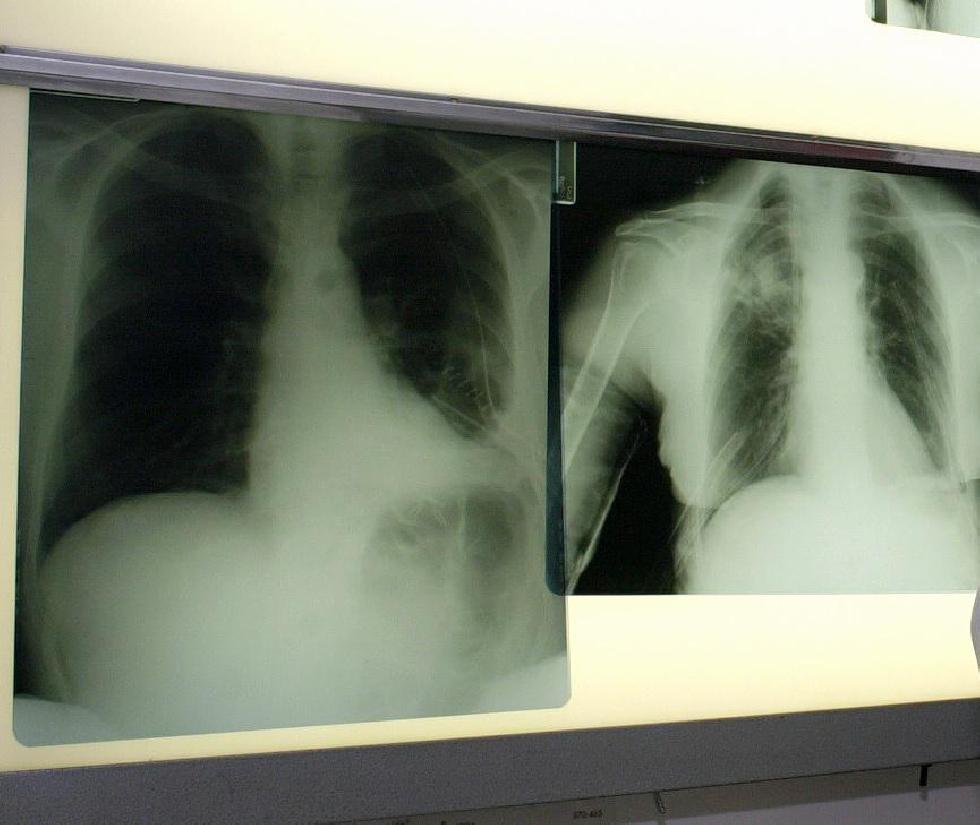

Roma, 29 set. (Adnkronos Salute) – Raccontare l’eterogeneità del tumore al polmone, una delle neoplasie big killer, con 34mila decessi in un anno in Italia, secondo il Rapporto Aiom 2020. E’ questo uno degli obiettivi della campagna ‘Tratti di Respiro’ che prende il via oggi. L’iniziativa di Roche, realizzata con il patrocinio delle Associazioni di pazienti Walce Onlus (Women against lung cancer in Europe) e Ipop Onlus (Insieme per i pazienti di oncologia polmonare), vuole sensibilizzare e accendere i riflettori sulla patologia in tutte le sue diverse forme, sull’importanza di una diagnosi precoce e accurata e sulle prospettive offerte dagli approcci terapeutici innovativi nell’oncologia polmonare.

Quando si parla di tumore al polmone – ricorda una nota – spesso ci si riferisce ad una singola patologia, ma in realtà esistono molteplici forme di carcinoma polmonare, ognuna caratterizzata da alcuni tratti distintivi. All’origine delle diverse tipologie di tumore ci sono spesso specifiche alterazioni genetiche, come la mutazione del gene Egfr e il riarrangiamento dei geni Alk e Ros1. Parallelamente, ogni storia di malattia è diversa dall’altra e ogni testimonianza è ricca di sfaccettature che contraddistinguono il cammino personale e unico di chi si trova ad affrontare una diagnosi di questo tipo.

“Nell’ambito della prevenzione, il fumo rimane uno dei principali fattori di rischio associati al tumore al polmone ed è importante sostenere e incentivare le Campagne di sensibilizzazione sui pericoli del fumo di sigaretta rivolte soprattutto ai giovani”, commenta Maria Rita Migliorino, responsabile Uosd di Pneumologia ad indirizzo oncologico dell’Azienda ospedaliera San Camillo-Forlanini di Roma e consigliere del direttivo di Walce Onlus. “Fortunatamente – osserva – sono stati realizzati grandi progressi nell’ambito della diagnosi e del trattamento di questa patologia, con l’individuazione di caratteristiche geniche della cellula tumorale che permettono una terapia sempre più personalizzata per ogni paziente. La ricerca e la determinazione di queste mutazioni, una sorta di ‘carta d’identità’ della malattia, consentono al clinico di indirizzare il paziente verso un percorso terapeutico personalizzato e appropriato”.